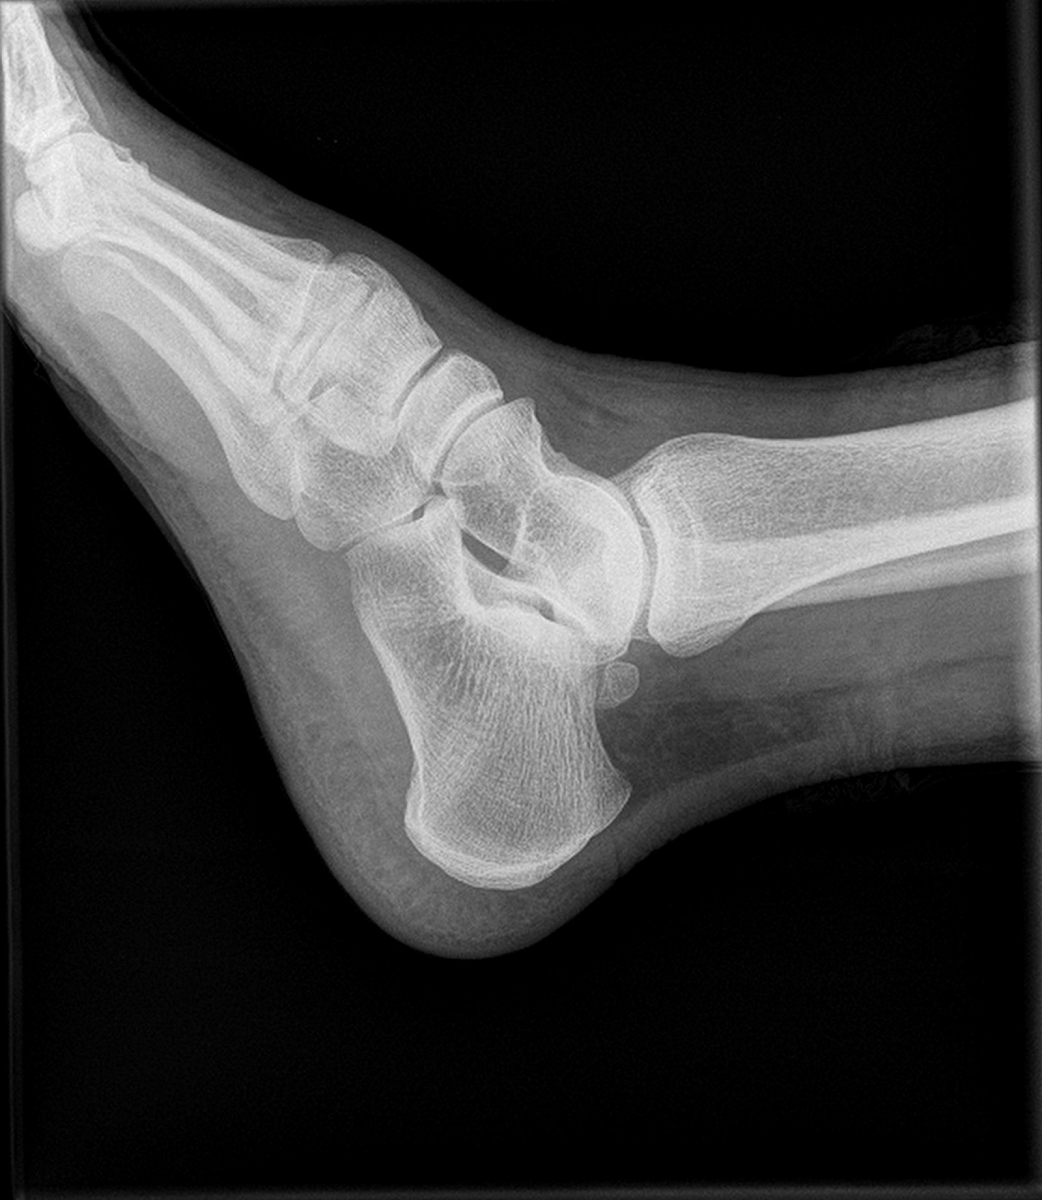

背景:区分软骨瘤和非典型软骨瘤(ACT)/软骨肉瘤是具有挑战性的。方法:为了评估放射学发现在区分软骨瘤和软骨肉瘤方面的诊断有用性,研究了各种放射学发现与最终诊断之间的相关性。基于这些相关性,开发了一个结合这些发现的评分系统。结果:在81名患者的队列中,X光上的骨膜反应、CT上的骨内凹陷和皮质缺损、骨外肿块、多叶状病变、MRI上邻近组织的异常信号以及骨扫描和铊扫描中的吸收增加与最终诊断显著相关。基于这些相关性,开发了一个结合放射学发现的放射学评分系统。在另一个由17名患者组成的队列中,放射学评分率在区分软骨瘤和软骨肉瘤方面的敏感性、特异性和准确性分别为88%、89%和88%。结论:建议进行综合评估,结合放射学发现,以区分软骨瘤和ACT/软骨肉瘤。

区分软骨瘤和非典型软骨瘤/软骨肉瘤的放射学评分系统